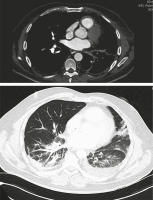

Computertomographie

Abbildung 4: Computertomographie April 2022

Keywords:

,

Pneumologie

Pulmonalvenenstenose

PVS